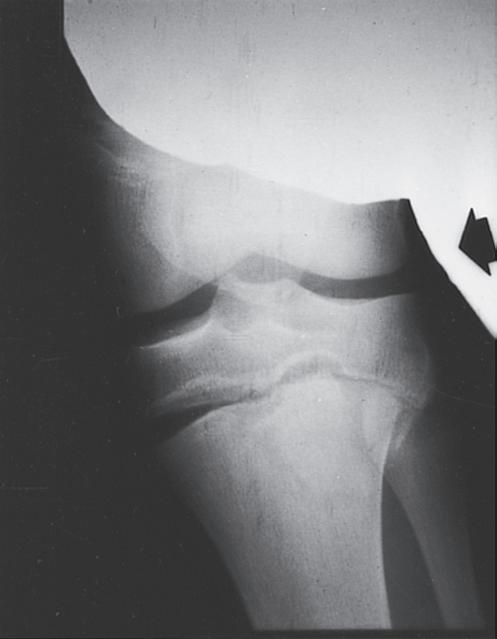

ANATOMIC DIFFERENCES OF PEDIATRIC BONES

As the skeleton of a child grows, it develops from a relatively elastic and rubbery type of biomechanical material to the more rigid structure of an adult skeleton. Because of the amount of radiolucent cartilaginous material in pediatric bone, comparison films are sometimes necessary to determine whether a radiograph is abnormal, and this lack of clarity in the radiograph can make diagnosis of fractures difficult. The types of injuries may also be different in children; for example, ligamentous injuries and dislocations are rare. Injuries around the knee frequently lead to ligamentous and meniscal injuries in adults. In children, the distal femoral or proximal tibial physis is more likely to be injured because it is the weak link (Fig. 1.7). Previously, stress radiographs were recommended, but these are usually unnecessary because the diagnosis can be made by a complete history and physical examination and confirmed at follow-up when radiographs demonstrate a widened physis consistent with a healing growth plate injury. Ligamentous injuries in skeletally immature children are uncommon, but they do occur and become more frequent in adolescence as

Fig. 1.7 Stress films illustrating injuries to the proximal tibial physis (A), the medial collateral ligament (B), and the distal femoral physis (C) in skeletally immature children. Stress films are no longer recommended. The diagnosis of a nondisplaced Salter I physeal fracture is made based on local tenderness and swelling over the physis.